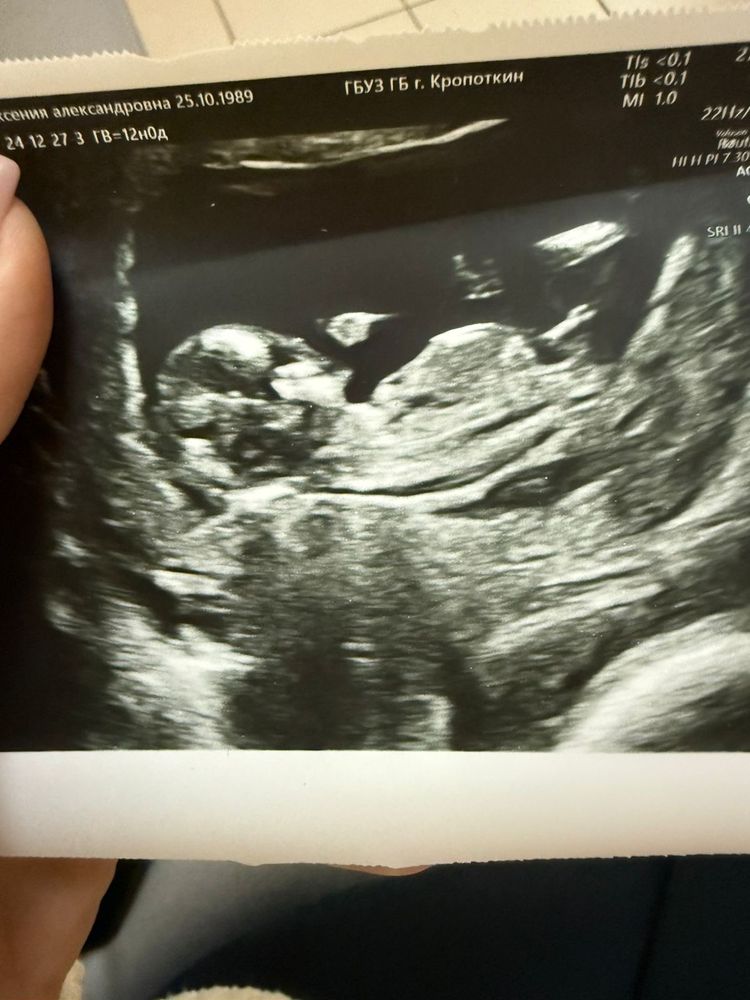

Угадываем пол по половому бугорку

У меня примерно такая же фотка была, дочка

Kris Ivanova, даа, сказал больше на мальчика похож

Kris Ivanova, я думаю у вас мальчик 😊

Elll, мне тоже так сказал, но так как была взволнована, то боюсь память меня может подводить) мб на самом деле он говорил, что у мальчиков более вздернутый бугорок, явно что это пацан он не сказал =D